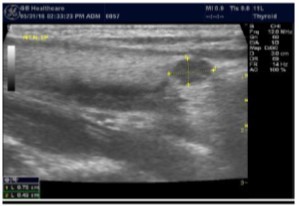

The superficial location of the thyroid gland renders it ideal for ultrasound examination 8. High resolution grey scale images can easily be obtained using high frequency transducer. In the transverse view, normal thyroid gland has the butter fly appearance, with left and right lobes connected with a narrow isthmus, Figure 1A. Both lobes can be imaged separately in the longitudinal plan, Figure 1B

Figure 1A.Normal thyroid gland transverse view